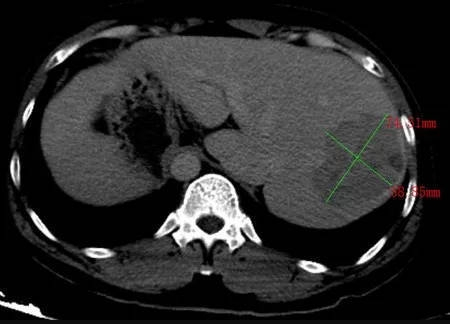

▲CT检查结果显示,跟正常人相比,李利的肝脏长反了。院方供图

由于缺乏体检意识,也没生过大病,李利此前从不知道自己竟然如此罕见。震惊之余,还有另一个更为致命的消息——他的肝脏有一个肿瘤。当地医院建议他立即到大医院做进一步检查。